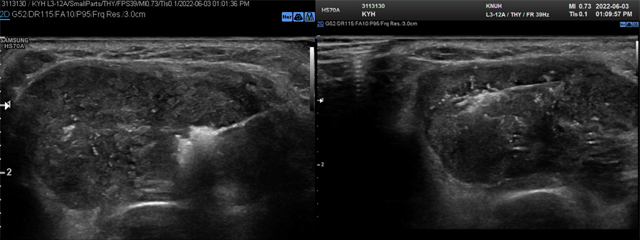

- (5) Moving-shot technique Electrode tip은 병변의 가장 깊고 먼 부위에 위치시키고 치료를 시작하는데, 고주파 세기는 30-50W에서 시작해 5-10초가 지나도 tip 주위로 echogenic zone이 생기지 않는다며 고주파 세기를 10W씩 올려줄 수 있다. 치료를 시행하는 동안 electrode tip의 위치는 결절 내에 고정하지 않고 이동시켜 주는데, 결절을 가상의 절제 단위로 나누어 가장 멀고 깊은 부위에서부터 가깝고 얕은 부분으로 이동하며 열소작을 시행해 결절 전체를 빠짐없이 치료해준다. 소작이 된 부분은 tip주위로 echogenic micro-bubble이 발생하는데 이때문에 한번 tip이 지나간 자리의 후방은 tip이 잘 보이지 않는다. 따라서 반드시 깊은 곳에서 얕은 곳으로 이동하며 소작을 시행해준다.

Fig. 3. Moving shot technique을 이용한 고주파 절제술 모습. 소작된 tip주위로 echogenic bubble이 발생한다.